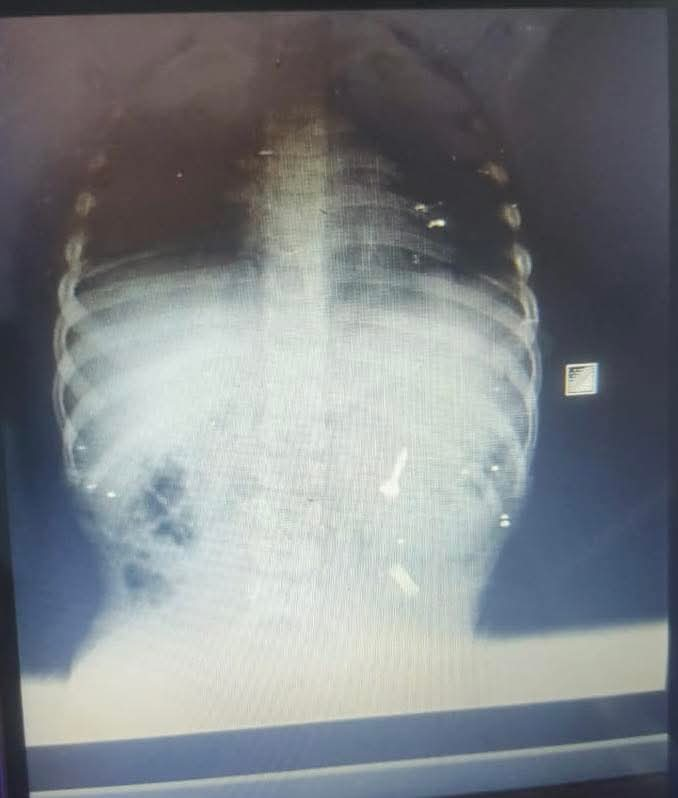

بدأت الأحداث في الساعات الأولى من صباح السبت، حين وصلت أسرة الطفل إلى قسم الطوارئ بمجمع الشفاء الطبي التابع للهيئة العامة للرعاية الصحية بفرع بورسعيد، وهي في حالة هلع شديد، ليتم استقباله فورًا وإجراء أشعة عاجلة على البطن لتحديد موقع الجسم الغريب.

وأظهرت الصور وجود المسمار في أول أجزاء الأمعاء الدقيقة المصران الصائم، وهو موقع يصعُب الوصول إليه بالمنظار نظرًا لوجود تعرجات وزوايا ضيقة، مما جعل احتمالات التنظير محدودة للغاية.